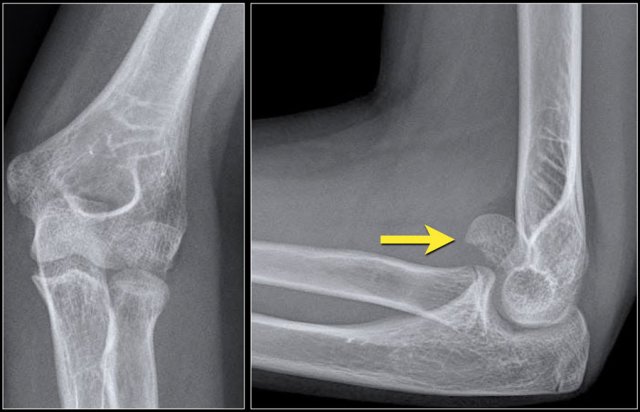

Capitellum fracture

While fractures of the lateral condyle occur in children between the age of 4 -10 years, isolated fractures of the capitellum are seen in children above the age of 12.

Capitellum fractures are uncommon.

The rotation of the fracture fragment gives a typical appearance on the X-rays (arrow).